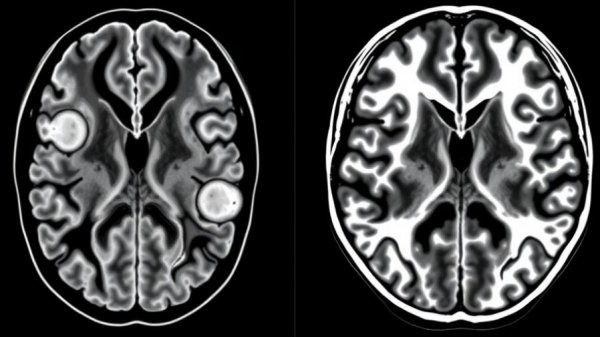

Recent reports have highlighted a troubling surge in cases of meningitis, a serious and potentially lethal infection. This emerging pathogen poses significant risks, particularly to vulnerable populations. As concierge health practitioners committed to providing top-tier care, it's vital to stay informed about such developments that could affect your patients. Meningitis can occur due to bacteria, viruses, or fungi, but increasing cases attributed to previously rare strains demand immediate attention.

The Importance of Early Diagnosis

Timely detection of meningitis symptoms can be life-saving. Symptoms often include fever, headache, stiff neck, and sensitivity to light. In cases of severe infection, it can escalate to seizures, coma, or even death. Given the rapid onset of these symptoms, close monitoring is essential for at-risk patients. Concierge practitioners, who generally have more personalized access to patient health data, are in a unique position to recognize these signs more promptly.